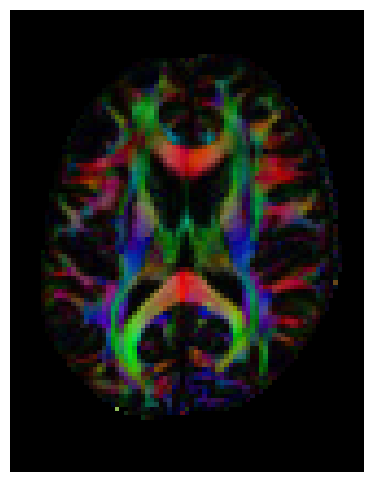

We can also compute the colored FA or RGB-map. First, FA needs tob e scaled between 0 and 1, then the RGB map can be computed and visualized.

FA = np.clip(FA, 0, 1)

RGB = color_fa(FA, tenfit.evecs)

plt.figure(figsize=(6, 6))

plt.imshow(np.rot90(RGB[:, :, sli, :], k=1)) # k=1 → 90° counterclockwise

plt.axis('off');

../../_images/d0b7715463be6ff446176b79f46d952c58f1d41bda4b511eb8556520c421739e.png